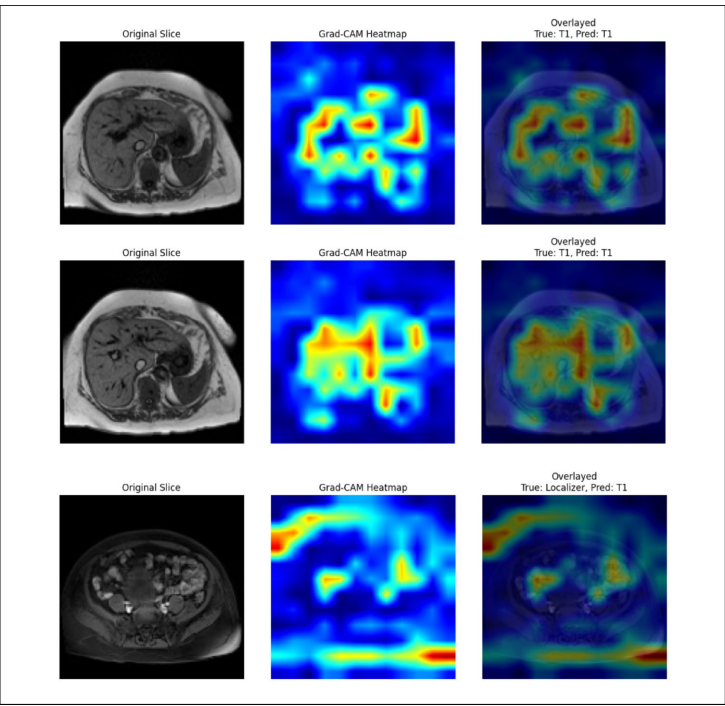

研究构建的12类脉冲序列分类模型在测试集达到99.51%的准确率。通过分析发现,局部定位器(Localizer)序列偶尔会被误判为T1加权像,这源于两者在快速梯度回波技术上的相似性。Grad-CAM可视化显示,模型在判断T1加权像时重点关注肝叶前部、胸主动脉及周围腹部脂肪区域,这些正是放射科医师常关注的诊断区域。

针对轴向(axial)、冠状(coronal)、矢状(sagittal)和N/A四类方位的分类模型表现更为出色,测试准确率达99.87%。值得注意的是,多数投票策略成功纠正了切片级别的个别误判,使体积级准确率达到完美水平。这种提升在临床环境中尤为重要,因为放射科医师通常基于完整序列而非单一切片进行诊断。